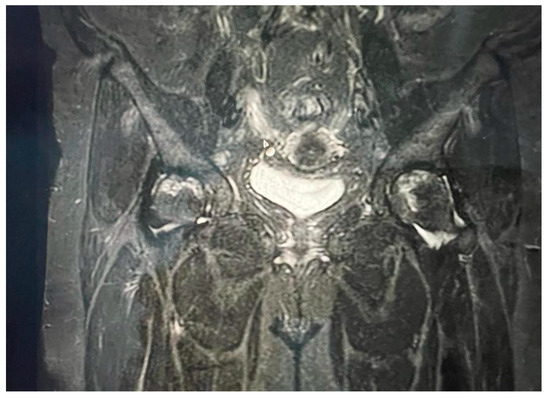

By adhering to stringent inclusion criteria and rigorous diagnostic standards, we sought to enhance the accuracy and validity of our analysis. This meticulous approach not only bolstered the credibility of our findings but also facilitated a comprehensive exploration of the intricate relationship between COVID-19 and avascular necrosis of the femoral head (Figure 1 and Figure 2).

Figure 1. Bilateral hip MRI with avascular necrosis.